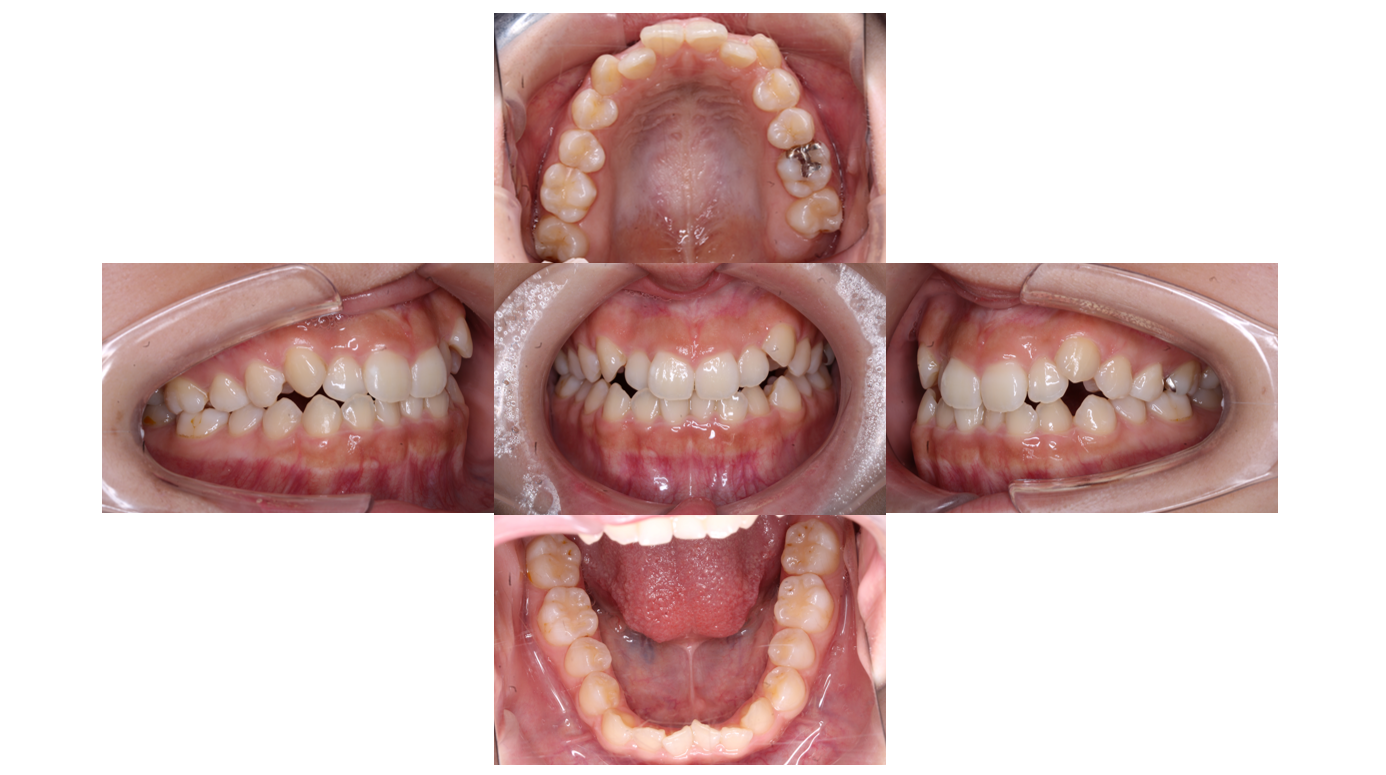

初診

Before

| 主訴 | 【主訴】八重歯が気になる 【診断・症状】上下凸凹 |

| 抜歯 | 非抜歯 |

| 矯正の装置 | ハーフリンガル矯正 |